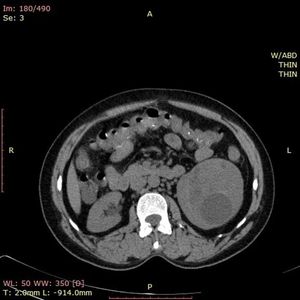

Case History: 45-year-old patient presented with history of abdominal discomfort.